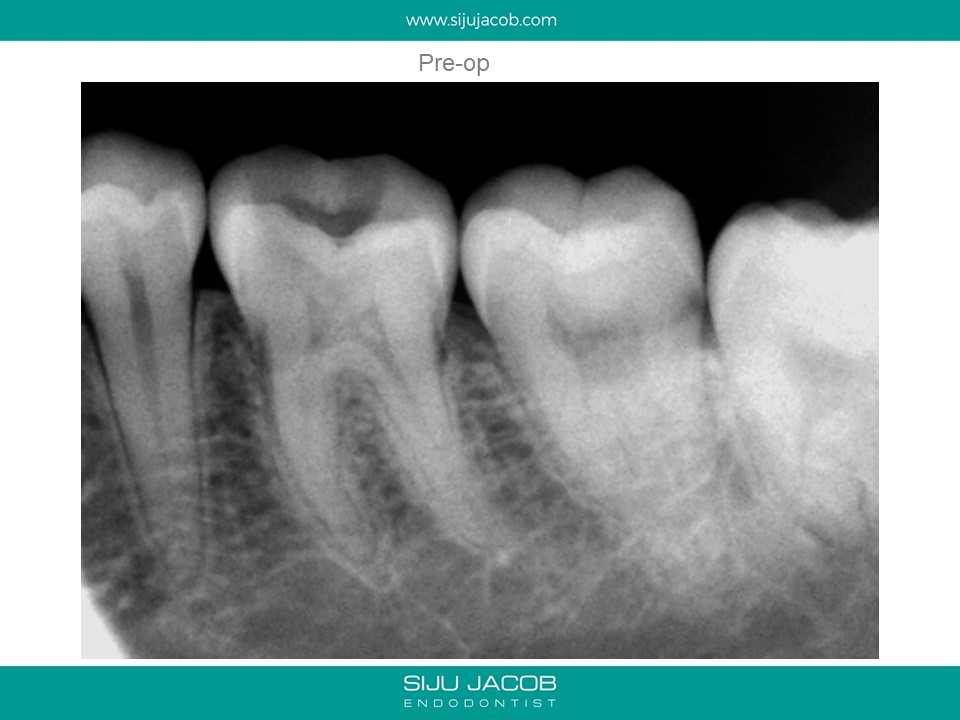

Whenever I get a case started by someone else, I warn the patient about the fact that I’m not really sure what the previous practitioner has done. Most times, the damage isn’t that bad. Occassionally, we get surprises like this one: A perforation.